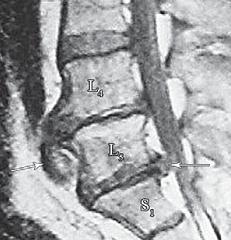

МРТ № 3

На МРТ № 3 — поясничный отдел позвоночника. (На данном «контрольном» снимке наблюдаются остаточные явления дегенеративно-дистрофического процесса в сегменте LV-SI после устранения методом вертеброревитологии секвестрированной грыжи межпозвонкового диска.)

В поясничном отделе форма позвоночного канала, создаваемая телом и дужками позвонка, вариабельна, но чаще она пятиугольная. В норме позвоночный канал в пояснично-крестцовом отделе сужен в переднезаднем диаметре на уровне LIII и LIV позвонков. Его диаметр каудально увеличивается, и поперечное сечение канала приобретает форму, близкую к треугольной, на уровне LV-SI. У женщин канал имеет тенденцию к расширению в нижней части крестцовой области. Сагиттальный диаметр значительно уменьшается от LI к LIII почти неизменен от LIII к LIV и увеличивается от LIV к LV. В норме переднезадний диаметр позвоночного канала в среднем равен 21 мм (15–25 мм).

Существует простая и удобная формула определения ширины позвоночного канала:

нормальный сагиттальный размер не менее 15 мм;

11–15 мм — относительный стеноз;

менее 10 мм — абсолютный стеноз. Уменьшение этого соотношения свидетельствует о сужении канала.

Высота поясничных межпозвонковых дисков 8–12 мм, нарастает от LI до LIV-LV, обычно уменьшается на уровне LV-SI